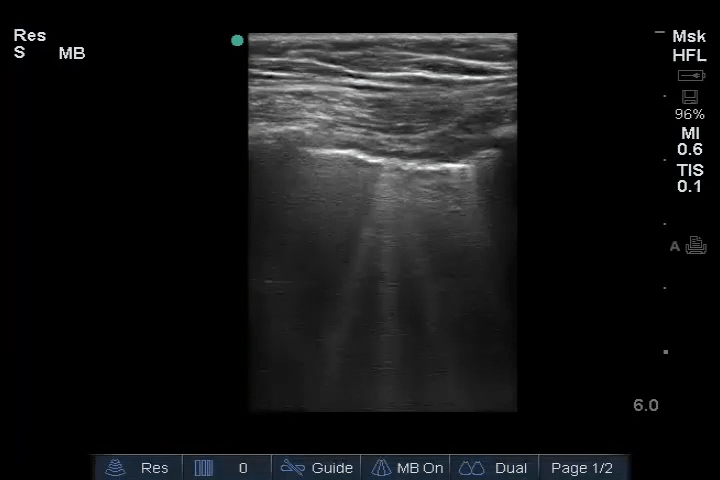

The following ultrasonographic signs are suggestive of pulmonary edema:

• Multiple B-lines (>2) between two costae in more than one view bilaterally

The following ultrasonographic signs rule out pulmonary edema:

• Absence of multiple B-lines between two costae in more than one view bilaterally